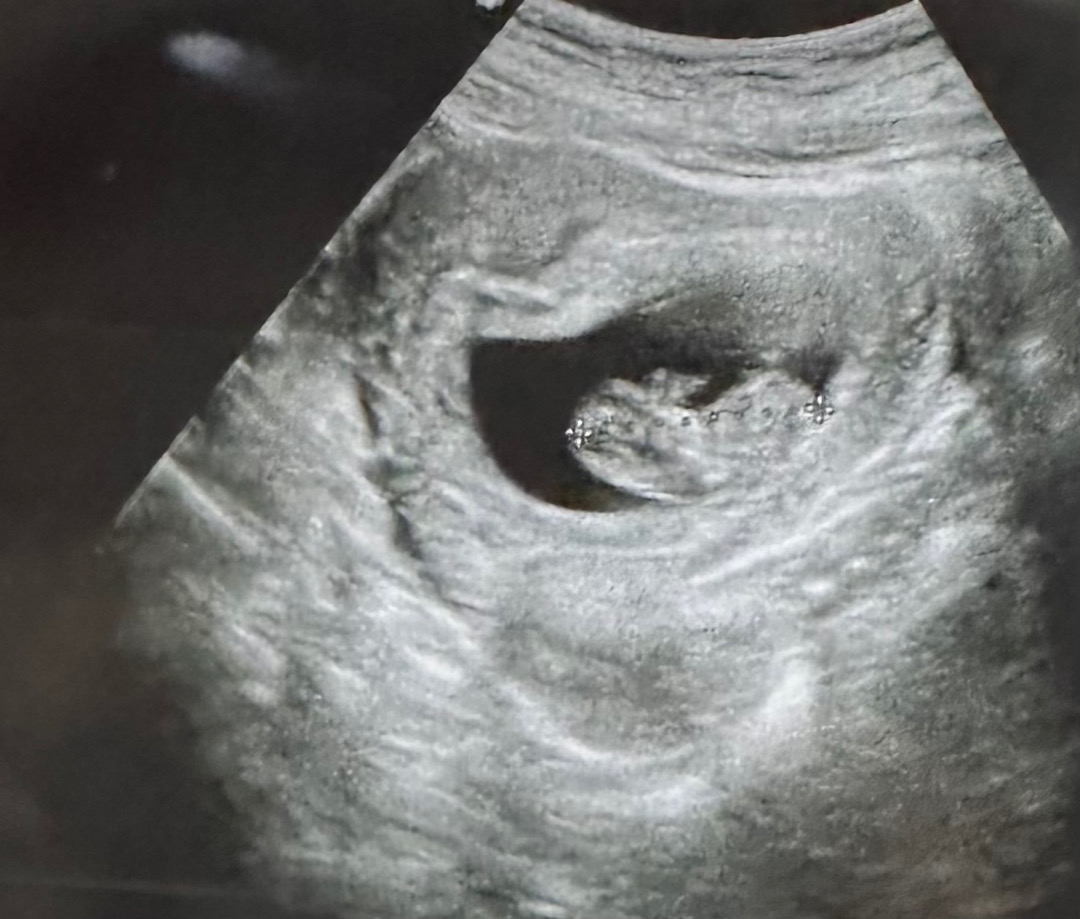

11주됐구 왼쪽이 머리쪽이래염 알려주실분.. 뭐가 보이시거나 각도로 아시는분...